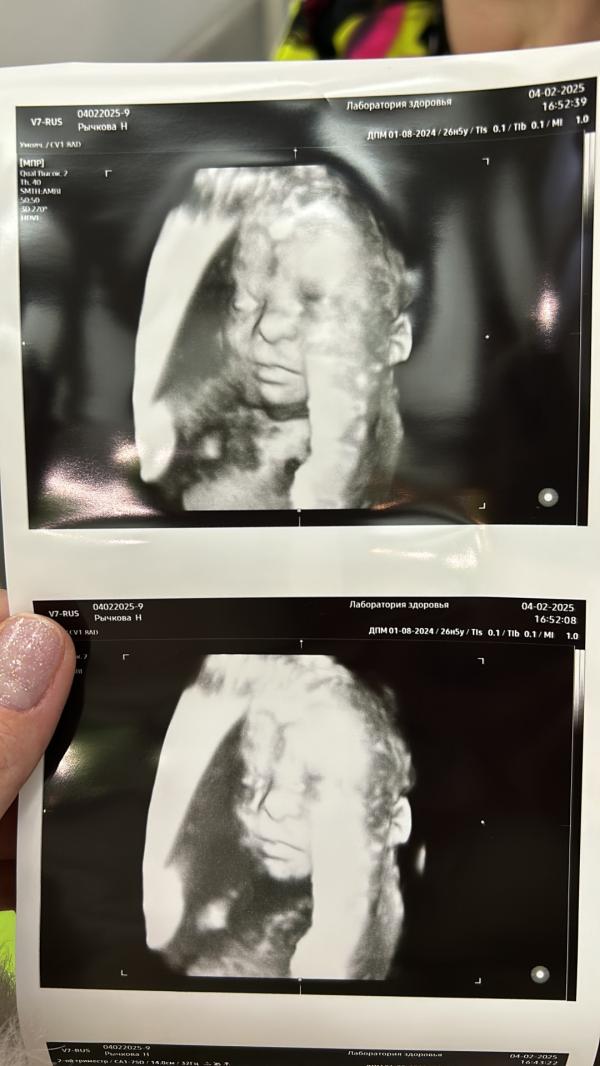

А фото прикрепляю своего сладкого малыша, я как увидела , поняла , как сильно я его уже люблю❤️